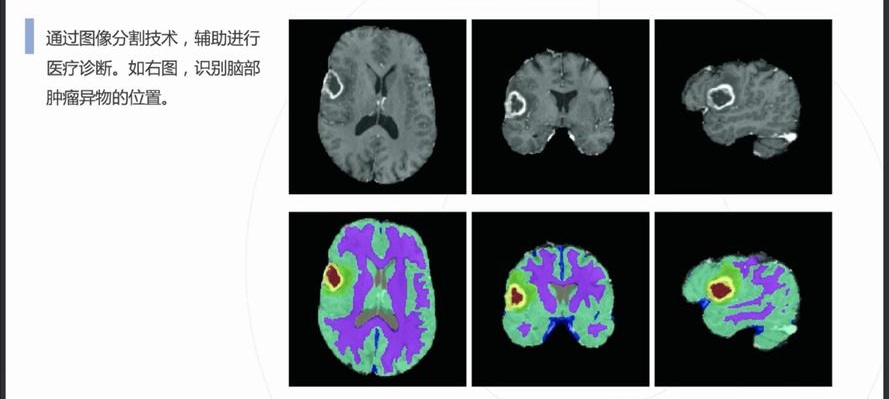

自動(dòng)病灶檢測(cè):借助計(jì)算機(jī)視覺和人工智能算法,CCD視覺檢測(cè)設(shè)備能夠自動(dòng)識(shí)別醫(yī)學(xué)影像中的病灶區(qū)域,如腫瘤、炎癥、骨折等異常結(jié)構(gòu)。

早期癌癥篩查:在乳腺癌、肺癌、皮膚癌等癌癥的早期篩查中,CCD視覺檢測(cè)系統(tǒng)通過分析X光、MRI或CT掃描圖像,識(shí)別出腫瘤的早期跡象,顯著提高早期診斷率。

精確測(cè)量與評(píng)估:CCD視覺檢測(cè)設(shè)備可對(duì)病灶的大小、形狀、位置等參數(shù)進(jìn)行精確測(cè)量,幫助醫(yī)生量化評(píng)估病情,制定更精準(zhǔn)的治療方案。